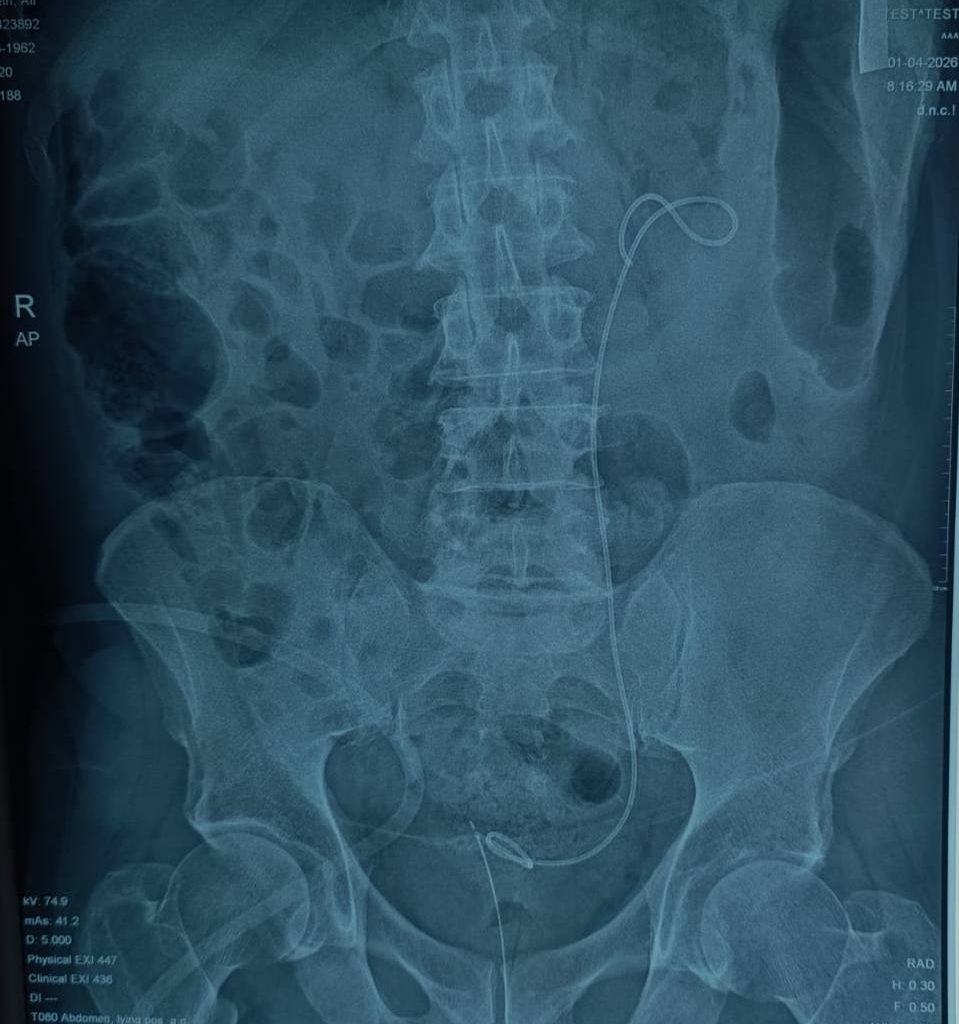

في قصة تحمل الكثير من الألم والأمل، تمكن فريق طبي في مستشفى الإمام الحجة (عج) الخيري من إنهاء معاناة مريض سبعيني قدم من محافظة مجاورة، بعد أشهر طويلة من الألم بسبب حصوة كلوية كبيرة في الكلية اليسرى، تجاوز حجمها 10 سم، وتسببت له بأعراض شديدة تمثلت بالغثيان والتقيؤ واضطراب في وظائف الكلية.

حيث نجح أخصائي جراحة المسالك البولية الدكتور أمير الأعرجي، وبمشاركة طبيب التخدير الدكتور عبد الأمير نوري، في إجراء عملية استخراج الحصوة باستخدام ناظور الكلية عن طريق الجلد، عبر شق جراحي صغير لا يتجاوز 1 سم، وبالاعتماد على التخدير المناطقي بدلًا من التخدير العام.

“كانت الحالة معقدة بسبب حجم الحصوة الكبير والوضع الصحي العام للمريض، لكن بعد تقييم دقيق وخطة مدروسة، تمكنا من إجراء العملية باستخدام تقنية الناظور عبر الجلد وتحت التخدير المناطقي لتقليل المخاطر إلى أدنى حد ممكن.”

“تم استخراج الحصوة بالكامل بنجاح، دون الحاجة إلى التخدير العام، وهو ما شكّل عامل أمان مهم في مثل هذه الحالات.”